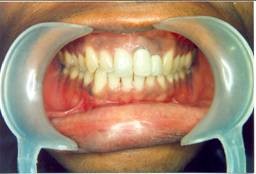

Our Treated Happy Patients